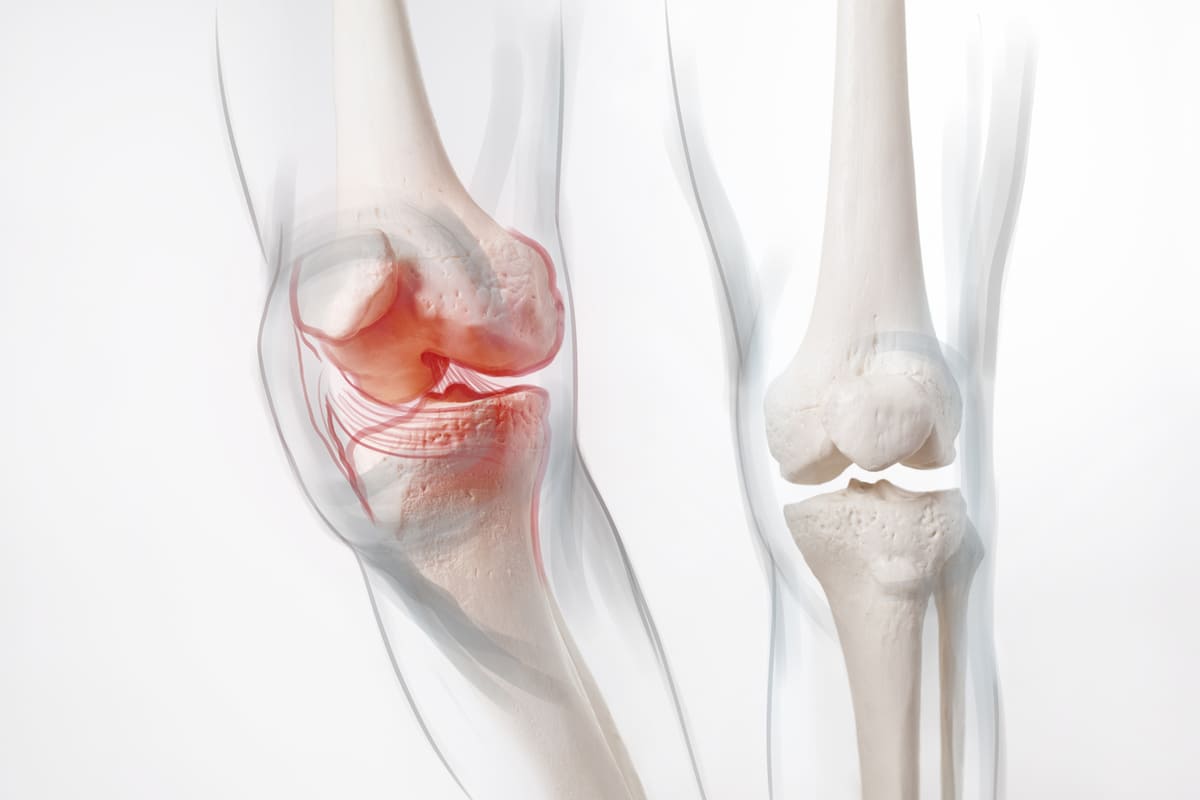

3. Bone Health and Vitamin D Absorption

Beyond its immune-boosting properties, vitamin D from cod liver oil plays a critical role in calcium absorption and bone health. Adequate vitamin D levels are essential for preventing conditions such as osteoporosis and ensuring the proper mineralization of bones. Regular supplementation with cod liver oil can be especially beneficial for individuals with limited sun exposure, as vitamin D is synthesized in the skin in response to sunlight.

4. Anti-Inflammatory Properties

The omega-3 fatty acids in cod liver oil exhibit potent anti-inflammatory properties. Chronic inflammation is linked to various health issues, including arthritis, autoimmune diseases, and cardiovascular diseases. By incorporating cod liver oil into your diet, you may help mitigate inflammation, potentially reducing the risk of chronic conditions and promoting overall wellness.